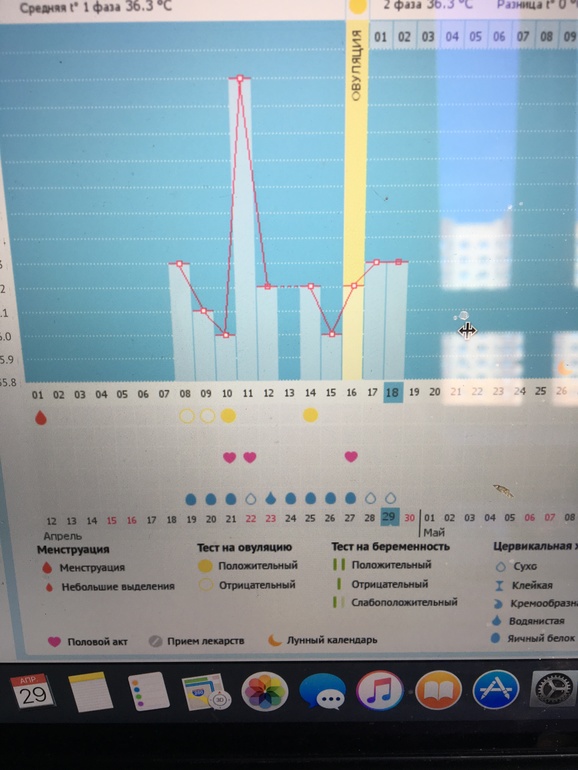

Девочки посмотрите мой график ну что за дурдом ? овуляция по узи подтверждено 27 числа

вроде на 27е ой короче что то вообще не получается разобраться

Ну вот. Уже лучше. Теперь температура должна повышаться.

вот поменяла вроде

ну вот так правильнее и то мне кажется, что она была 24-25, для узи как раз это "только была", но может и 27, это уже не так важно, должна подняться ваша БТ) ждите, удачи)

27 уже было жт а вокруг него жидкость врач сказала овуляция только только